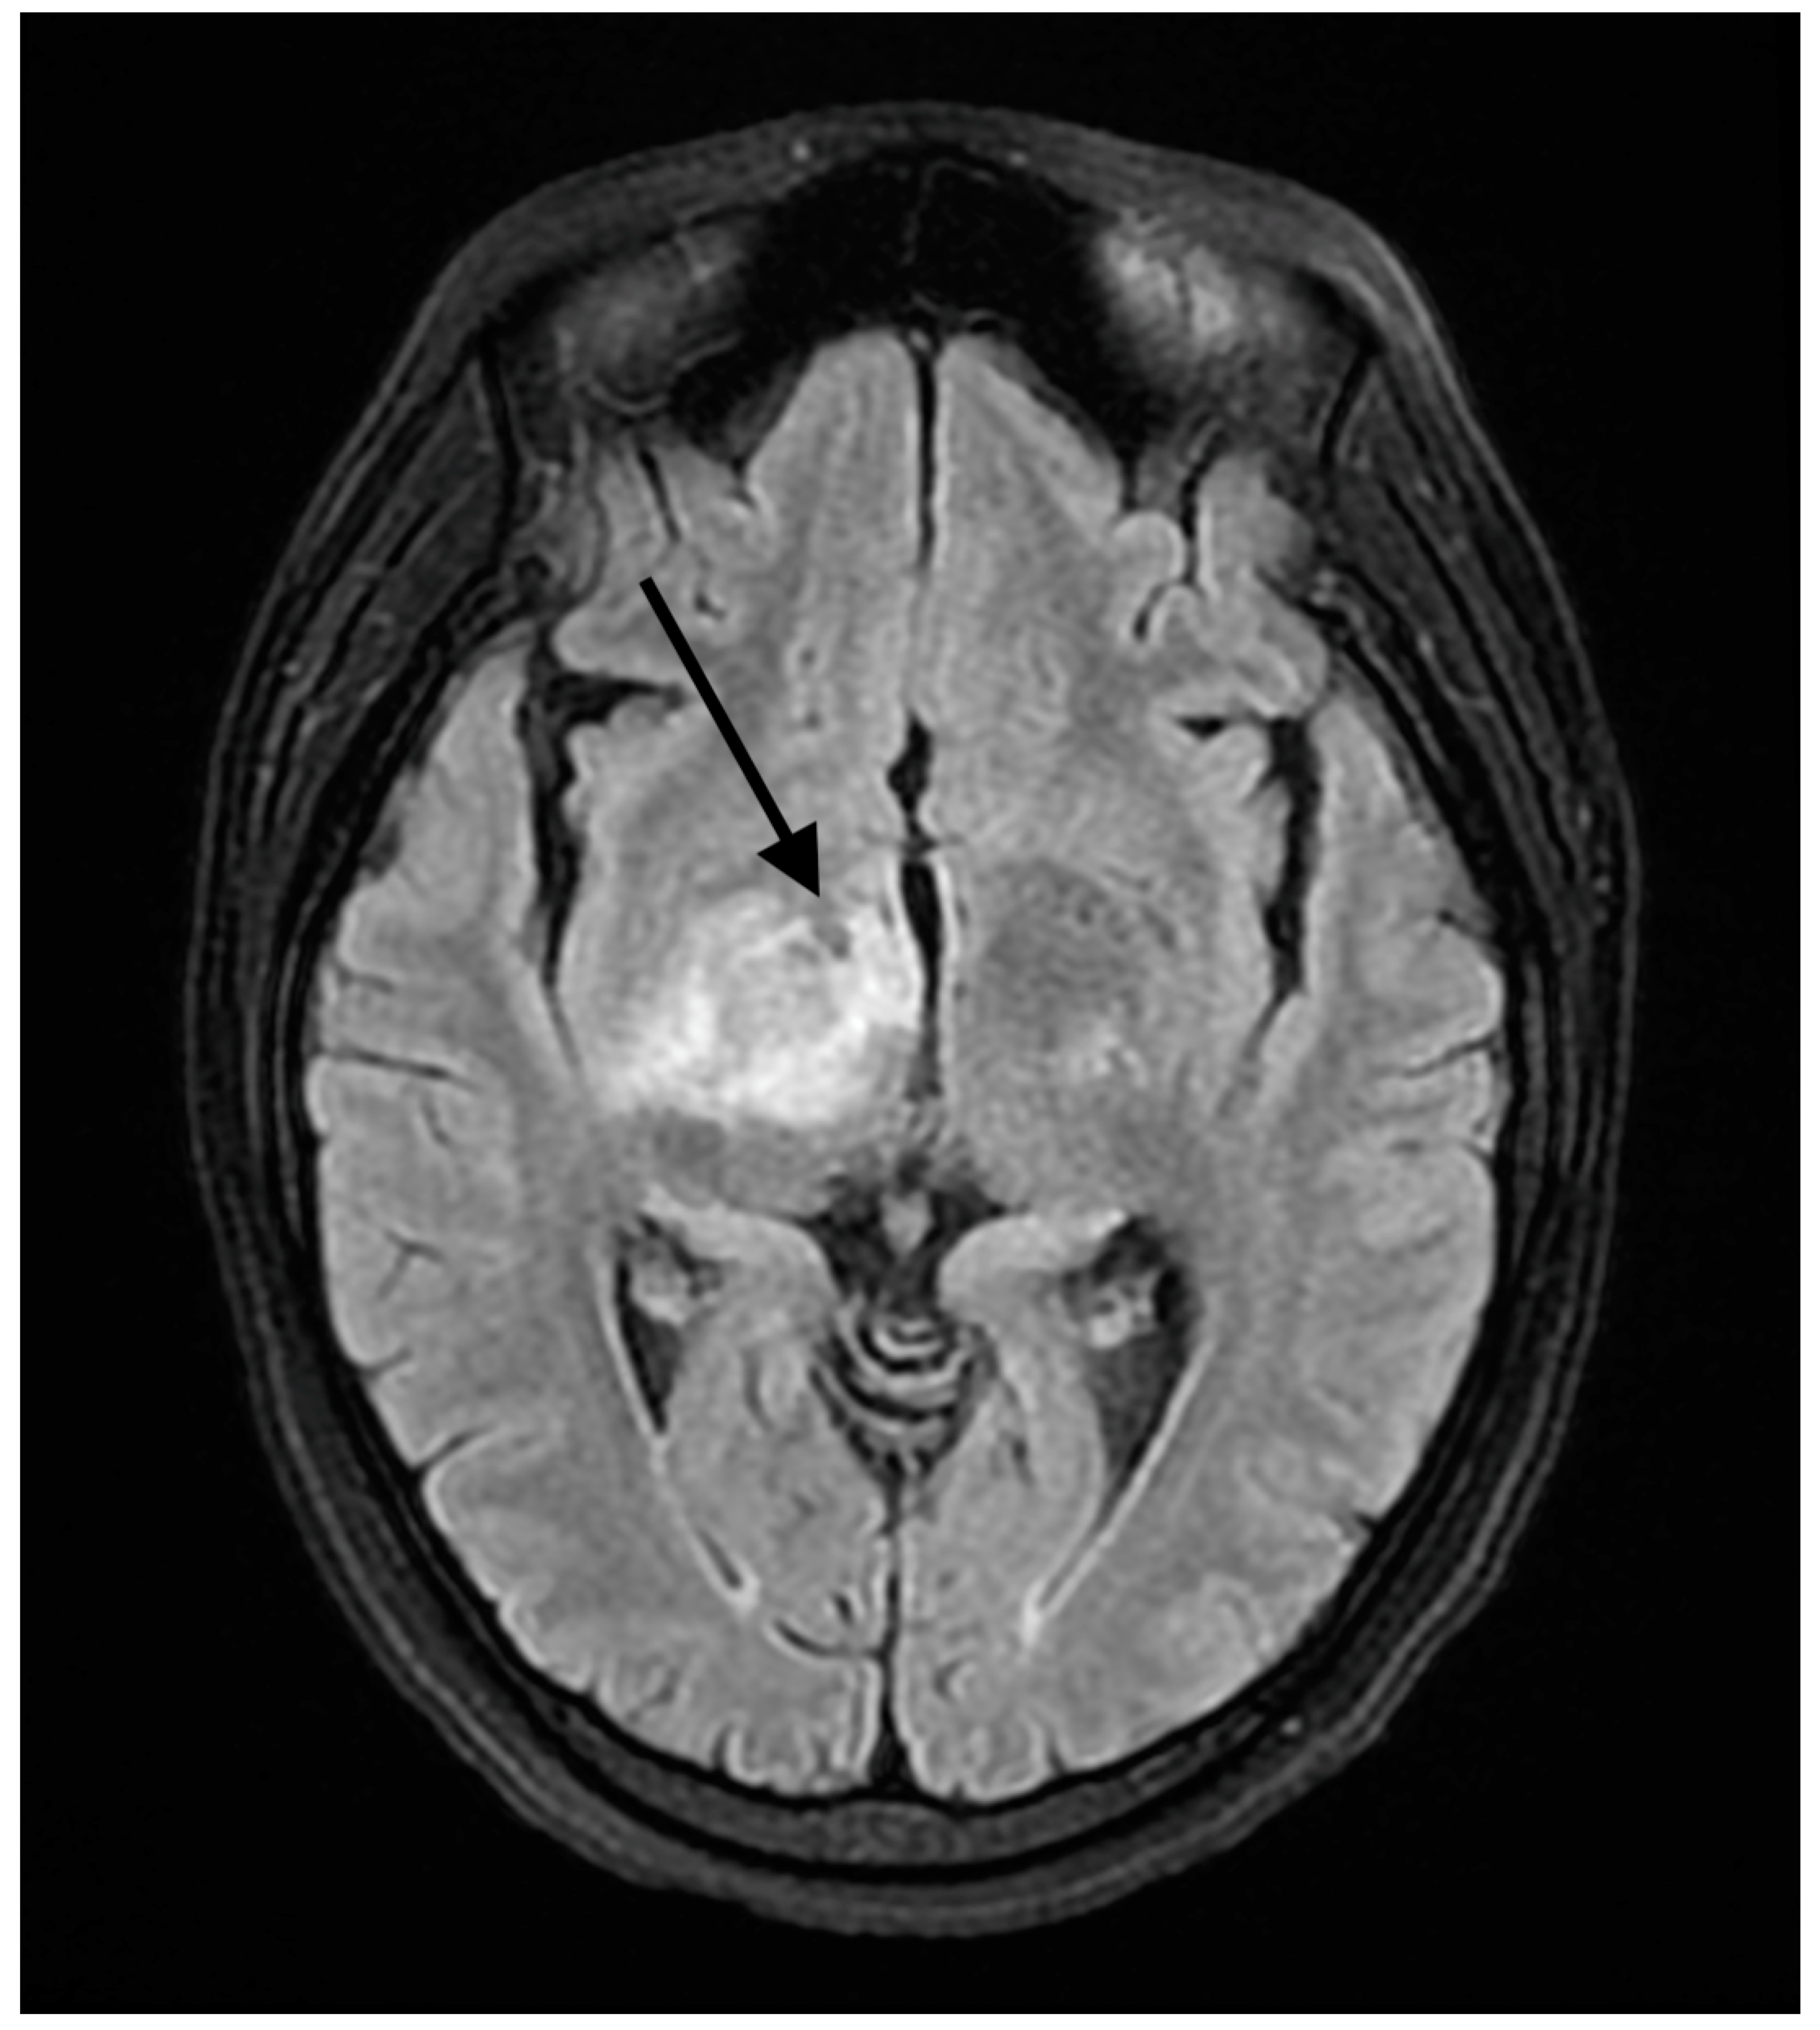

2. Detailed Case Description